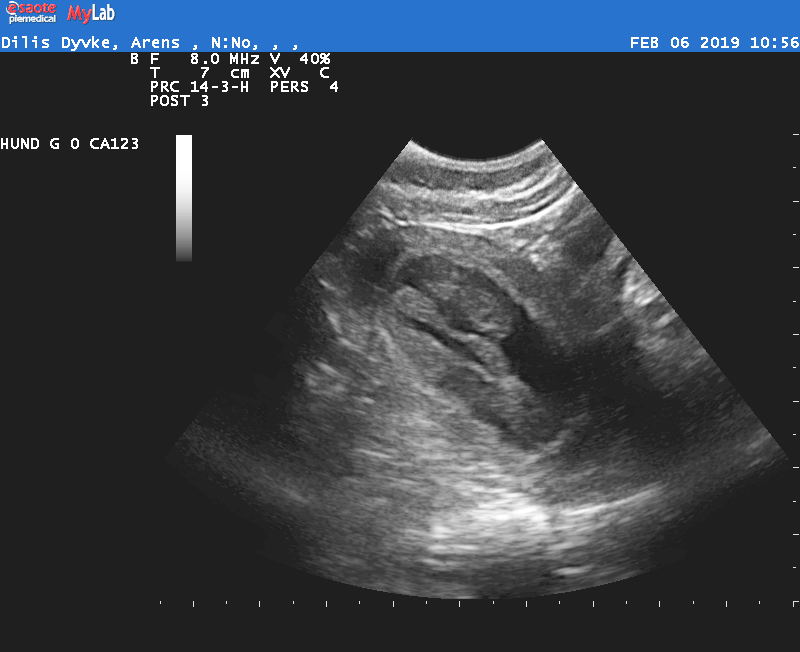

07.02.2019 Heute waren wir mit Dyvke beim Ultraschall. Wie jedes Mal eine spannende Angelegenheit: Ist sie oder ist sie nicht? Sie ist!!! Megaglücklich freuen wir uns auf eine hoffentlich gesunde Welpenschar im März.

Dyvke bringt 13,1kg auf die Waage und hüpft noch rum als wäre nichts